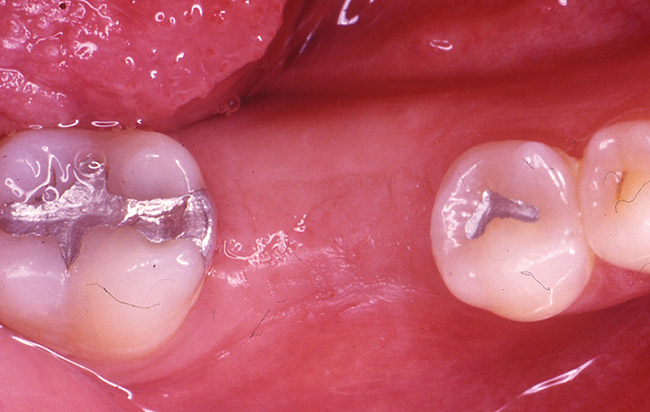

The patient was a 65-year-old healthy man who was referred for a periodontal evaluation of tooth No. 28. The patient presented with the chief complaint of pain and swelling in the lower right side of his mandible. Clinical examination revealed deep probing depth primarily (9 mm) on the distal-facial aspect of tooth No. 28. The tooth presented with grade 2 mobility. A periapical radio­graph of the tooth revealed the presence of a radiolucent appearance that was more significant at the midroot level (Figure 2A). The prognosis was determined to be "hopeless" because of a root fracture.

The patient was scheduled for extraction of the tooth, along with socket preservation. After extraction, the socket was curetted. Bone loss on the buccal aspect as a result of infected tissue was noted (Figure 2B). After socket curettage, the socket was grafted using a combination of freeze-dried bone allograft combined with a calcium sulfate bone graft barrier (Figure 2C). The patient was placed on antibiotic and anti-inflammatory medications. Six months after the socket preservation procedure, the site was prepared for implant placement. At the time of implant placement, a core of bone was harvested from the socket preservation site and analyzed histologically (Figure 2D and Figure 2E).

The histology report included the presence of viable bone consisting of anastomosing trabeculae surrounding Haversian systems. The Haversian systems contain connective tissue with variably sized, endothelial-lined vascular spaces. The bone formation is primarily lamellar. Osteocytes are present within the lacunae. Abundant fibrous connective tissue is present at the periphery of this soft-tissue specimen, and woven bone is observed in the dense connective tissue. Fragments of calcified debris are admixed with the periphery of this decalcified specimen. The viable bone exhibits prominent resting and reversal lines. A diagnosis of viable sclerotic bone was made.

Implant placement was completed uneventfully, and after a healing period of about 3 months the implant was restored. The patient's tooth has been restored for about 5 years (Figure 2F).

Case 3: Extraction with Socket Preservation

The patient was a 55-year-old woman referred for evaluation of tooth No. 30 (Figure 3A). The tooth presented with a fractured root and was deemed nonrestorable. After a full thickness flap elevation, tooth No. 30 was extracted using an elevator and forceps. It was decided to preserve the socket because the site was planned to have an implant-supported restoration. The socket was grafted using freeze-dried bone allograft mixed with CAPSET (calcium sulfate bone graft barrier).a The socket was allowed to heal for 4 months (Figure 3B). After the healing period, the patient was scheduled to have an implant placed (Figure 3C). At the time of placement, it was noted that the bone appeared to be dense and firm to the touch. The implant was placed uneventfully (Figure 3D) and was successfully restored after a 3-month healing period. The patient has been followed for over 3 years and is functioning well using the implant-supported restoration.

Cases 2 and 3 illustrate the authors' current protocol for socket preservation, which includes atraumatic tooth extractions using periotomes and elevators as required. After the extraction, the socket wall is checked to evaluate the width of the bone. Typically when the bone is thin (< 2 mm on the buccal and lingual aspects), the socket is preserved using a combination of a freeze-dried bone graft material and a protective membrane. The choice of bone grafting materials and membranes may vary and the individual practitioner may have a particular combination that is most successful. Evidence from routine clinical practice indicates that socket preservation significantly benefits maintenance of ridge dimensions and ultimately the successful completion of implant-supported restorations.

Figure 3a  Tooth No. 30 presented with a fractured root deemed nonrestorable.

Figure 3a

Figure 3b  The socket was grafted using freeze-dried bone allograft mixed with CAPSET. The socket was allowed to heal for 4 months.

Figure 3b

Figure 3c  After the healing period, the patient had an implant placed.

Figure 3c

Figure 3d  The implant was placed uneventfully and was successfully restored after a 3-month healing period.

Figure 3d